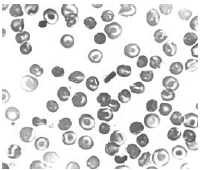

A figura mostra um esfregaço sanguíneo, cuja morfologia dos eritrócitos é encontrada nos pacientes com Hemoglobinopatia C homozigótica.

Na figura, observa-se um esfregaço sanguíneo com morfologia dos eritrócitos característica de paciente com Anemia Falciforme.